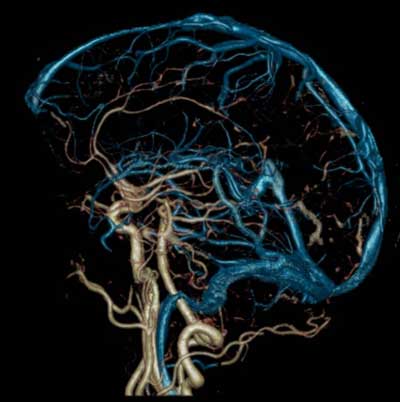

Из чего состоит Виллизиев круг

Прежде всего, стоит понять, что такое Виллизиев круг. Это сеть артерий в мозге, имеющая форму овального венца. Данное название было дано в честь его первооткрывателя — Томаса Виллиса.

Круг формируется за счет следующих артерий:

- Задняя соединительная артерия.

- Задняя мозговая артерия.

- Передняя мозговая артерия.

- Внутренние сонные артерии.

Такое анатомическое строение позволяет соединять две основные системы: позвоночную и сонную.